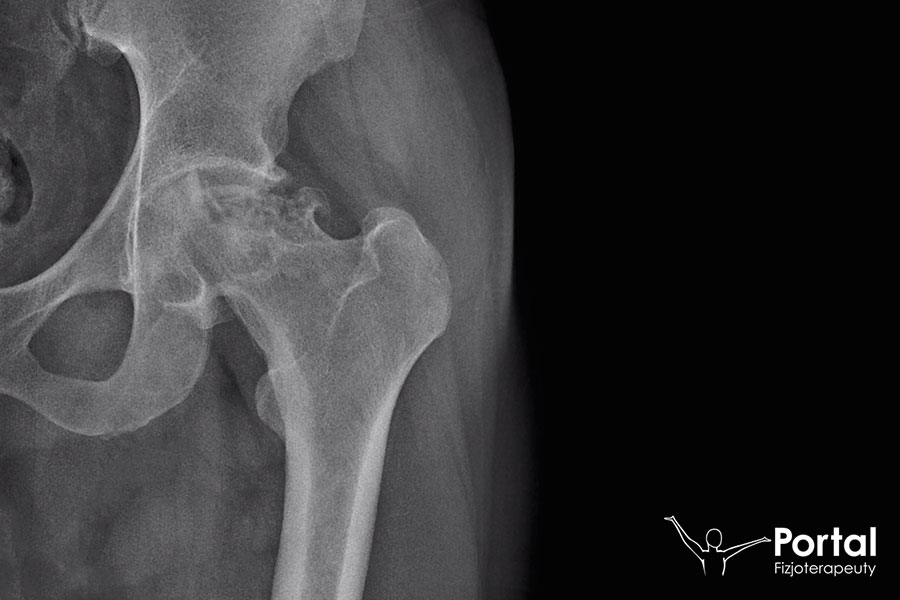

Epifizjoliza

Epifizjoliza (inaczej: młodzieńcze złuszczenie głowy kości udowej) dotyczy stawu biodrowego i jest rzadkim typem martwicy kości, charakteryzującym się jednostronnym lub